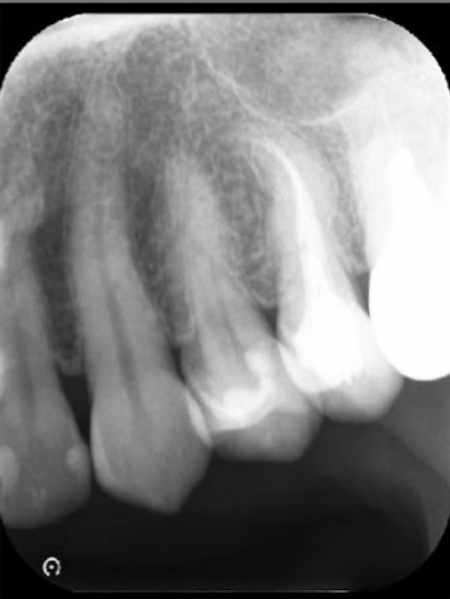

レントゲン検査を行って詳しく調べた結果、歯の根の先に歯の頭と同程度の大きさの根尖病巣(こんせんびょうそう)が確認できました。

根尖病巣とは歯の根の先にできる膿の袋のような病変です。

歯の内部の神経や血管が通る細い管に細菌感染が起こり、その影響が根の先に広がることで生じます。

まず、右上前歯の裏側に小さな穴を開け、そこから根管内にアプローチします。

マイクロスコープを使用しながら、細い器具を用いて根管内の感染した組織を取り除き、洗浄液で内部を洗い流しました。

感染組織の除去と洗浄を何回か繰り返し、根管内が清潔になったことを確認したうえで、再び細菌が侵入しないよう専用の薬を詰めました。

その後、歯の内部を補強するために土台となる支柱を設置し、歯科用の白い樹脂「コンポジットレジン」を用いて穴を塞ぎました。

治療終了から2年後のレントゲン画像です。根尖病巣が改善しています。